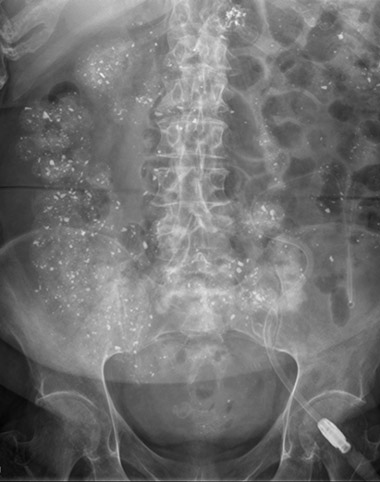

A 66-year-old woman on peritoneal dialysis for end-stage renal disease secondary to diabetic nephropathy was admitted on Christmas Day with suspected osteomyelitis of her left third toe. During admission, she complained of constipation and mild abdominal pain. There were no focal abdominal findings on examination. Of note, she was prescribed 750 mg three times daily of the rare metal lanthanum carbonate hydrate for hyperphosphataemia of renal failure. An abdominal x-ray was taken after the second dose of the day (Figure).

Lanthanum has been shown to be radio-opaque on x-ray1,2 and computed tomography,3 and this is briefly mentioned in the full product information. The radiology report in this case suggested alternative diagnoses of residual contrast from a barium study, sclerosing peritonitis, tuberculosis or lead ingestion, none of which were consistent with the clinical history.